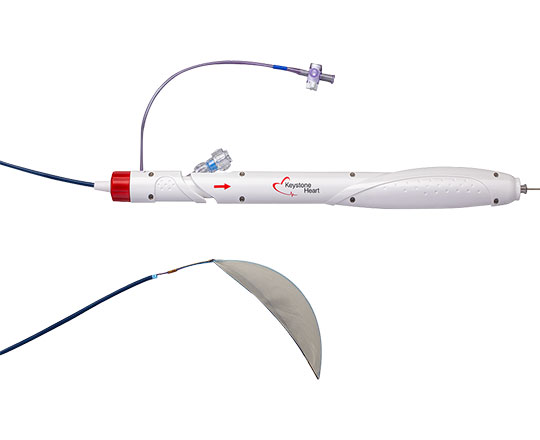

El dispositivo Conformal (Conformal Medical, Estados Unidos) está diseñado para adaptarse a la anatomía de la orejuela de cada paciente y disminuir la necesidad de ecografías transesofágicas y anestesia general durante el implante.

Tiene un esqueleto de nitinol con dos filas de 20 anclajes que se fijan a la pared de la orejuela, con un recubrimiento matricial de espuma en forma de tapón. En la parte superior de este, la expuesta al contacto sanguíneo, lleva un recubrimiento con tejido de politetrafluoroetileno expandido (ePTFE) que evita la trombosis del dispositivo1.

La matriz de espuma permite sellar con mayor eficacia posibles fugas de otros dispositivos, y se adapta a la mayor parte de anatomías de la orejuela con solo dos tamaños. La gran ventaja del recubrimiento de ePTFE es que reduce de manera importante la formación de trombos sobre el dispositivo, sobre todo cuando la anticoagulación o la antiagregación están contraindicadas.